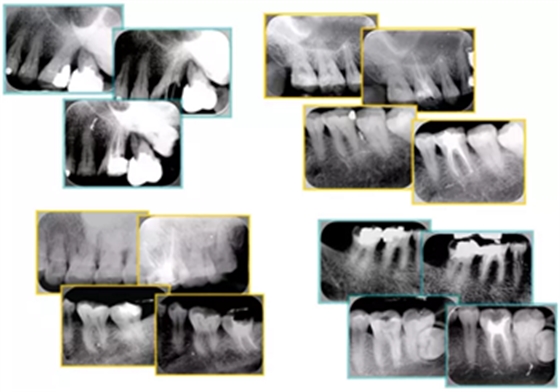

常見不良根管充填物有干髓、塑化、塑化 + 根充和不良根充。

上圖為干髓治療后牙齒,齲齒疏通后進(jìn)行根管充填。

如圖為塑化加根充處理后牙齒 X 線片。

常見有修復(fù)性鈣化和增齡性鈣化。下面為根管鈣化 X 線片。

右圖及下圖為器械折斷的 X 線片。箭頭處示折斷器械。